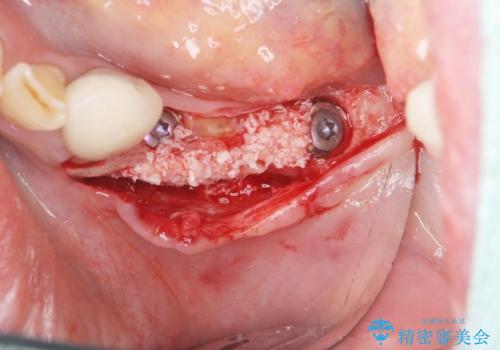

- 歯を失い噛むことができないことを悲観され来院されました。

他院で作製した入れ歯も嘔吐反射により気持ち悪くてはめていることができず、残存した右側の歯の負担は甚大です。

咬合機能を回復し、満足して食事を行えるようインプラント治療を計画します。

そのような場合、歯牙欠損状態の放置もしくはインプラント治療の選択になりますが残っている歯への負担も大きいためインプラント治療による咬合機能回復を推奨しております。